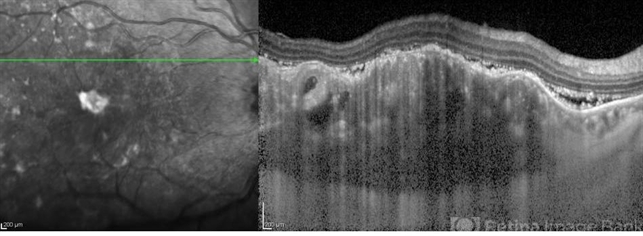

- choroidal metastasis, optical coherence tomography (OCT), enhanced depth imaging

- Enhanced depth OCT image of the macula of a patient with diffuse choroidal metastasis and exudative retinal detachment from breast carcinoma.